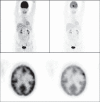

Accurate diagnosis and staging are essential for the optimal management of cancer patients. Positron emission tomography with 2-deoxy-2-[fluorine-18]fluoro-D-glucose integrated with computed tomography (18F-FDG PET/CT) has emerged as a powerful imaging tool for the detection of various cancers. The combined acquisition of PET and CT has synergistic advantages over PET or CT alone and minimizes their individual limitations. It is a valuable tool for staging and restaging of some tumors and has an important role in the detection of recurrence in asymptomatic patients with rising tumor marker levels and patients with negative or equivocal findings on conventional imaging techniques. It also allows for monitoring response to therapy and permitting timely modification of therapeutic regimens. In about 27% of the patients, the course of management is changed. This review provides guidance for oncologists/radiotherapists and clinical and surgical specialists on the use of 18F-FDG PET/CT in oncology.